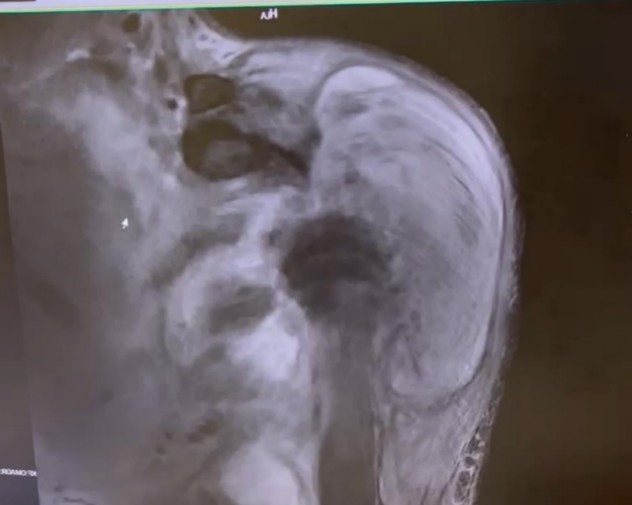

另一方面,手术前需要更清晰的影像资料来制定手术方案,但王哥每次做磁共振等检查时,都会不由自主地浑身发抖(心理障碍导致),没有办法完成磁共振检查,影像学上根本无法清晰呈现他目前整个右肩关节肿瘤的情况。同时,肿瘤也破坏了肩胛骨的关节盂,侵犯了肱骨近端周围的所有肌腱韧带,就算切除了肿瘤,如何重建一个稳定的肩关节,也是很大的困难。

放射科刘主任带领放射科团队凭借丰富的经验,为王哥尽可能拍到了部分清晰的磁共振影像,为精准制定手术方案奠定了基础。随后,骨科、血管外科、放射科专家团队联合为王哥进行了手术。先堵住那些给肿瘤“输血”的血管,降低术中大出血风险;在肿瘤包裹的最主要动脉血管里植入支架,放置阻断球囊,防止发生大出血,对右手臂的主要动脉进行保护;再剥离、完整切除这个排球大小的肿瘤。 由于肿瘤侵犯了肩关节囊的所有肌肉肩袖组织,王主任将肱骨连同周围的肿瘤组织完整切除,然后用反肩人工假体对王哥的肩关节进行了重建。同时手术室、麻醉科、输血科也对手术的安全顺利完成进行了全力保障。